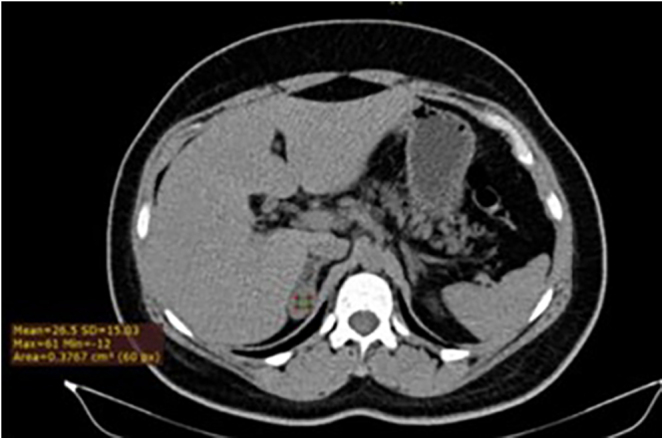

Summary: A 39 year old female with signs of hyperandrogenism, was diagnosed with congenital adrenal hyperplasia after a cortrosyn test. Abdominal tomography showed a nodular image in the right adrenal gland, measuring 1.9 × 3.1 cm, 26 UH. Screening for Cushing's syndrome and pheochromocytoma was negative. Due to the maternal family history of MEN2A, RET gene testing was performed (positive), and screening for medullary thyroid carcinoma (MTC) with calcitonin was <2 pg/mL. As the patient's father passed away due to complications of peptic ulcers and hailed from a region with high rates of MEN1, PTH and calcium levels were checked, confirming the diagnosis of primary hyperparathyroidism (pHPT). Genetic investigation for MEN1 was positive, and an MRI of the pituitary gland revealed a non-producing macroadenoma. Management of pHPT and total prophylactic thyroidectomy were recommended, with an expectant approach regarding the adrenal lesion. Histopathological examination of the thyroid revealed papillary microcarcinoma in the right lobe and parafollicular cell hyperplasia in two foci, with immunohistochemistry consistent with MTC.